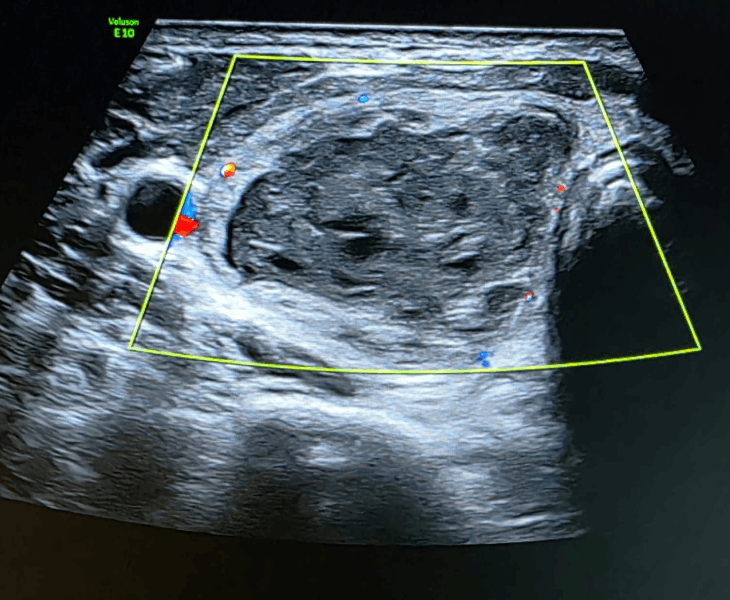

Follow‑up ultrasound typically shows reduction in size and reduced or absent vascularity within the nodule as it shrinks.

- Microwave ablation: for solid tissue (or residual solid component), a thin microwave probe is used to ablate the nodule from within, leading to gradual shrinkage.